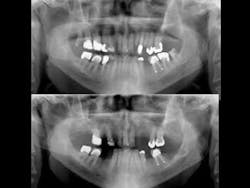

The most popular brands of RMGI restorative material are Ketac™ Nano from 3M ESPE, and FUJI II™ LC and FUJI Filling™ LC from GC (Figures 1 and 2). These materials have been used for restoration of highly caries–active patients such as bulimics, radiation–therapy patients, chemotherapy patients, or those with senile caries (Figures 3 and 4) with notable clinical success. Empirical evidence has convinced me of the cariostatic properties of the RMGI restorative materials.